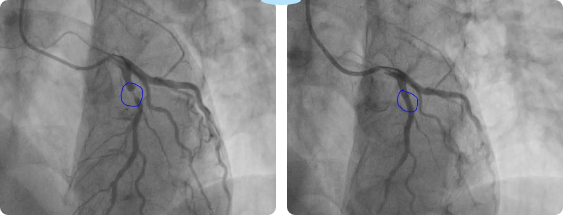

入院后,完善术前检查,术中造影显示前降支近端可见狭窄,最窄约95-99%;右侧冠脉近端可见支架内再狭窄,最窄约80%。病情凶险,随时可发生心脏骤停、恶性心律失常、心脏破裂等风险。心内一科主任杨海燕带领医师团队认真分析病情,决定行冠脉介入治疗,并对手术中可能出现的风险做好相关应急预案。

患者前降支及右冠均有狭窄,均有手术指征,由于“罪犯”血管为前降支,故于前降支成功植入支架一枚;择期处理右冠。